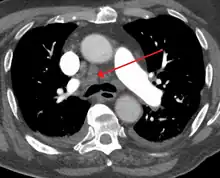

![]() 3D rendering of a high resolution computed tomography of the thorax, with mediastinum marked in blue. | |

![]() Mediastinum. The division between superior and inferior is at the sternal angle. | |